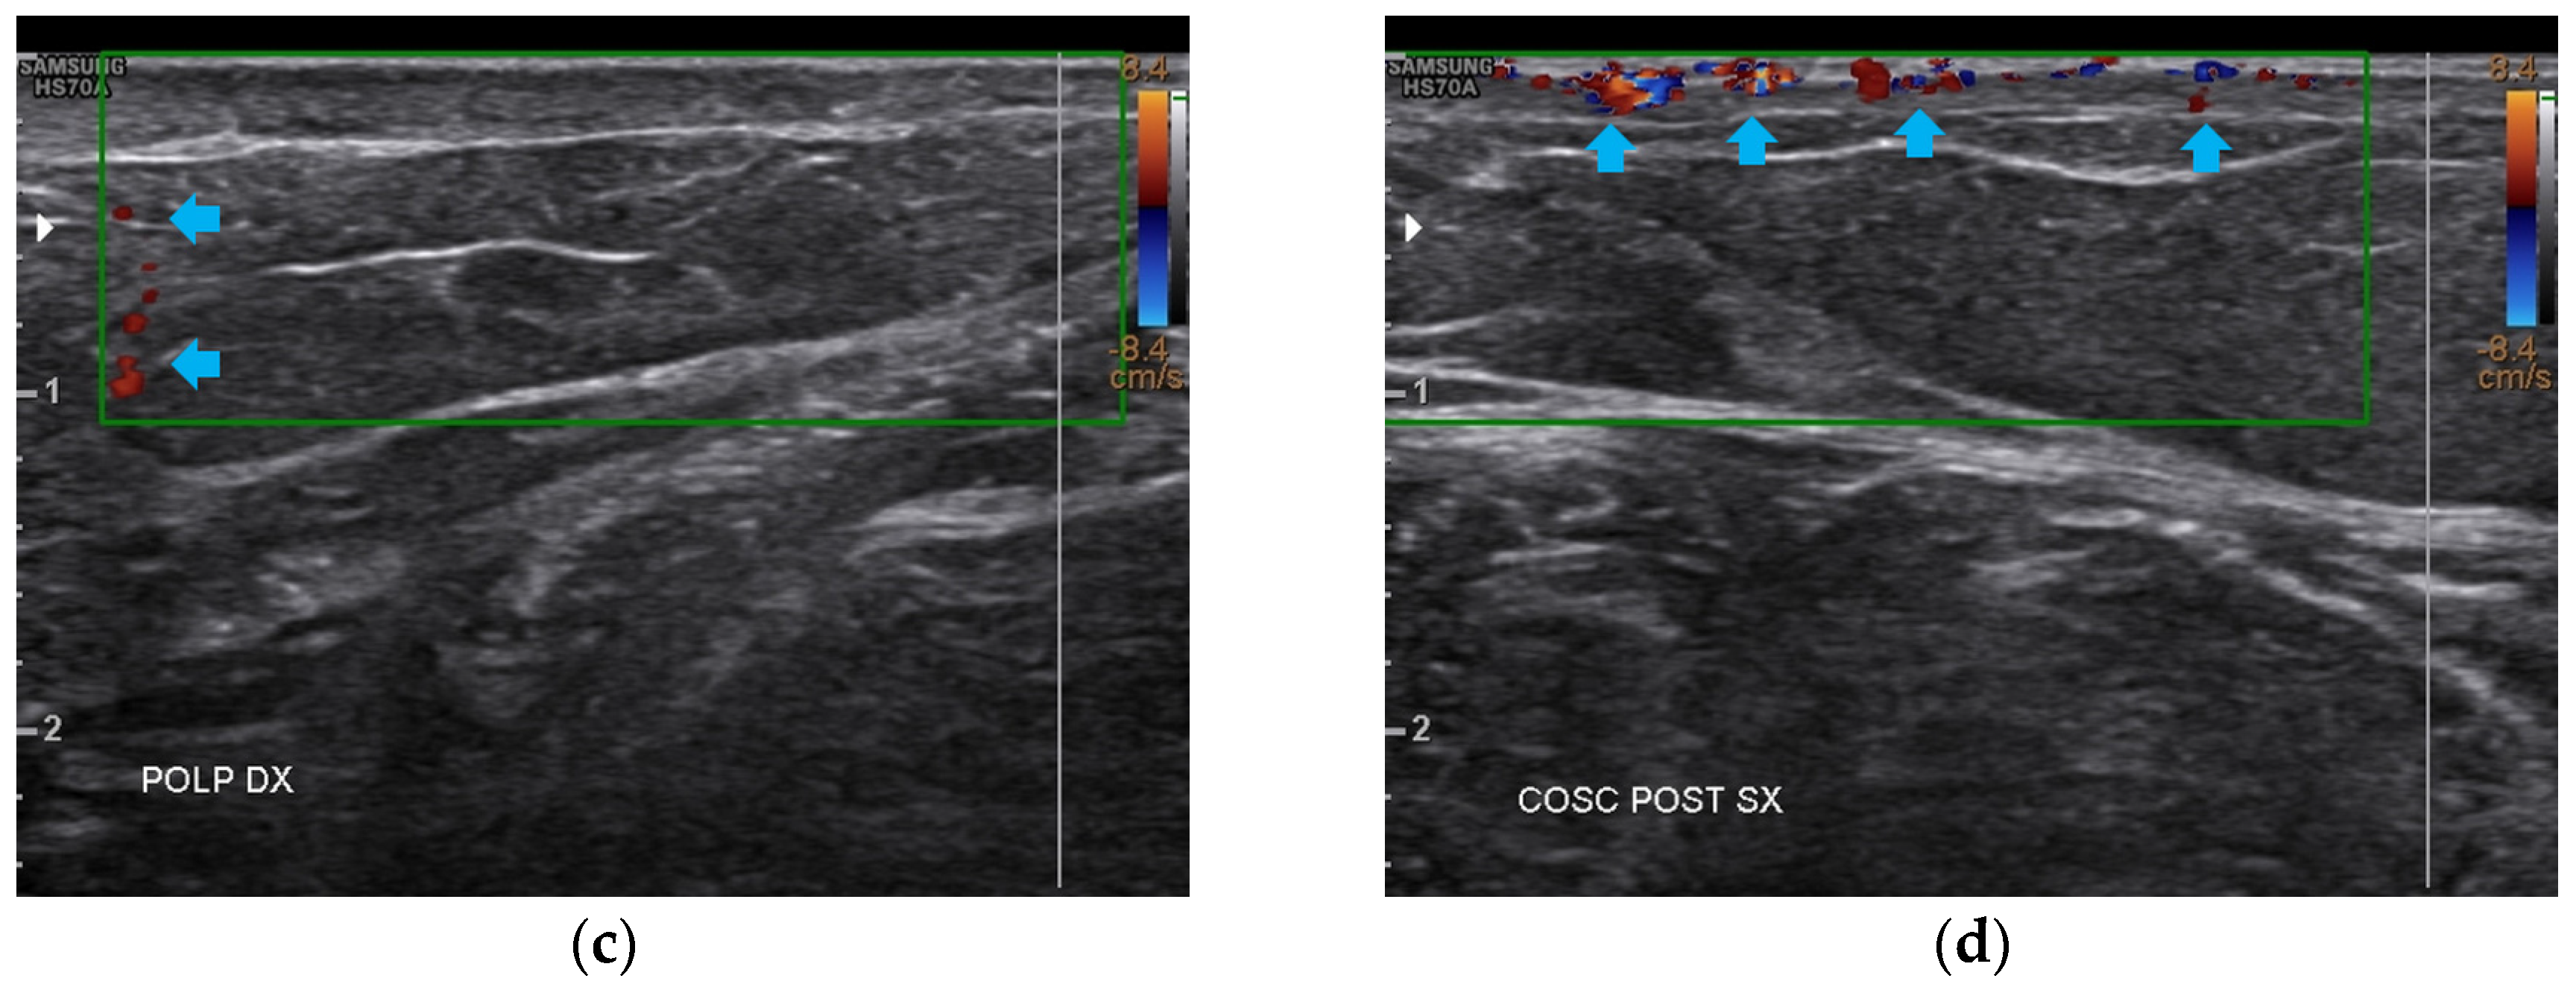

3.1. Basal Imaging Evaluations

3.2. Imaging Evaluations After the Treatment